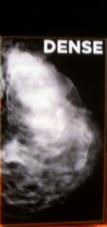

Not long ago I wrote about dense breasts being considered a risk factor for breast cancer.

“Your mammogram shows that your breast tissue is dense. Dense breast tissue is very common and is not abnormal. However, dense breast tissue can make it harder to find cancer on a mammogram and may also be associated with an increased risk of breast cancer.